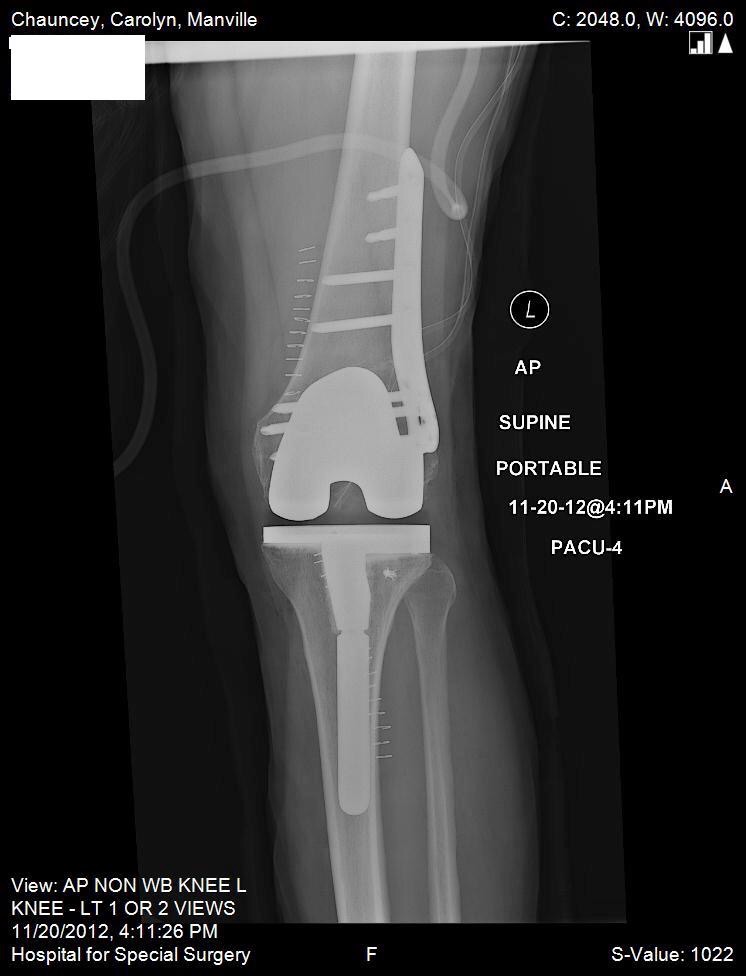

The events that transpired since my horrific ski accident left me feeling as though I would never walk again much less ski with my children. I had shattered both my tibia and fibula and 8 surgeries prior to visiting Dr. Fragomen's office. It has now been 9 months since my last surgery and I wanted to tell you about a magical time my family just had together. We are at Sunday River, a ski resort in Maine, I have donned my skis, and am skiing with my 11 year-old daughter, who wants to be a professional snow board rider when she grows up. This has been a very special weekend. This weekend also served as a trial run, as Cathy and I are getting married, slopeside, on December 28. All four of our children will be present. All this has been made possible by the hard work of you and all your colleagues at Hospital for Special Surgery. Without the dedication of your group, I am convinced prosthesis was in my future. It is with special gratitude that I write this letter, if there is ever anything I can do for your practice or for you personally, please feel free to contact me.